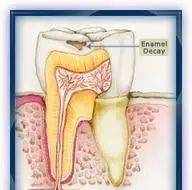

釉质龋

脱矿没有及时修复,牙齿表面开始缺损,就成为我们说的蛀牙、牙洞了。

早期的龋齿患者是没有感觉的,因此容易出现拖延,导致错过治疗的最佳时期。

在龋坏未累及牙神经时,单纯的补牙就足以解决问题。